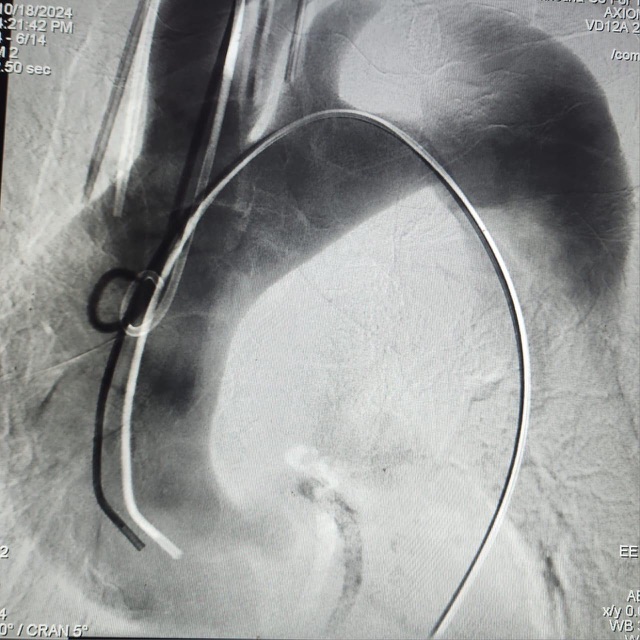

نجح فريق جراحة الأوعية الدموية بمستشفى طيبة التخصصي بإسنا، التابع للهيئة العامة للرعاية الصحية بمحافظة الأقصر، للمرة الأولى بحنوب الصعيد، في إجراء عملية تصحيح انشطار بالشريان الأورطى بالصدر لسيدة تبلغ من العمر 78 عاما.

وقال بيان لهيئة الرعاية، إن السيدة حضرت إلى المستشفى تعاني من ارتفاع بضغط الدم تسبب فى حدوث انشطار كلي وتمدد بالشريان الأورطى الهابط بالصدر حتى مستوى شرايين الكلى والأمعاء، مسببا لها آلاما شديدة بالصدر، وعدم القدرة على النوم بشكل طبيعي، منذرا بحدوث انفجار بالشريان الأورطى بالصدر.

وأضاف البيان: علاوة على توقف الدورة الدموية للسيدة عن بعض الأعضاء الحيوية، مثل المخ والنخاع الشوكي والكلى والكبد والأمعاء، مما قد يؤدي إلى حدوث الوفاة أو فشل في وظائف الأعضاء المذكورة، وتعرض المريضة لعدم القدرة على الحركة.

وأشار البيان إلى أنه على الفور اجتمع فريق جراحة الأوعية الدموية بالمستشفى لدراسة الحالة، وجرى تحديد الإجراءات الطبية اللازمة، وتم إتخاذ قرار اجراء الجراحة بتقنية التيفار TEVAR.

يذكر أن تكلفة هذه الجراحة تتخطى الـ 800 ألف جنيه، وتم إجراءها تحت مظلة التامين الصحي الشامل، ولم تدفع المريضه أكثر من 450 جنيها.